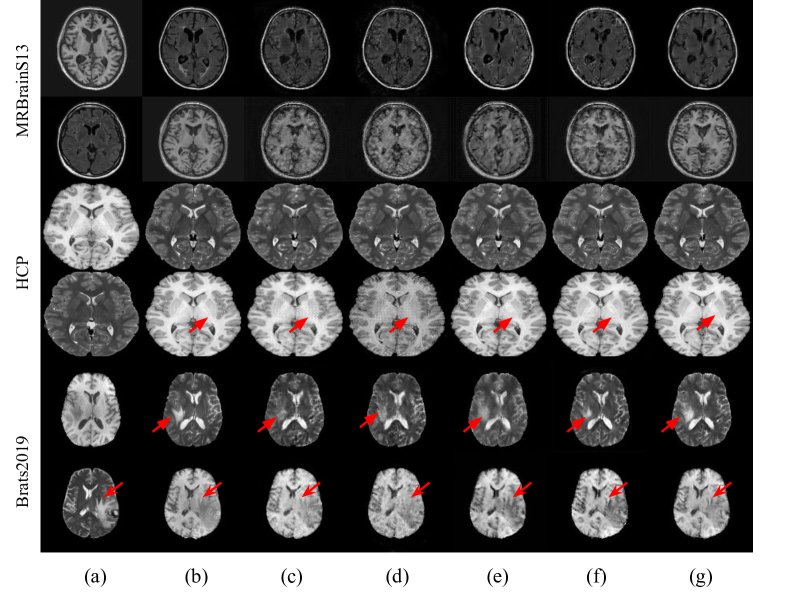

Fig. 4 illustrates the image translation on different datasets. The proposed methods (in the last column) provided a better synthetic image, resulting in better MSE, SSIM and PSNR scores. For example, the proposed synthetic T2 image provides a high qualitatively difference along the tumor boundary (indicated by the red arrows in the fifth row) than in existing methods using the available source T1 image as input.